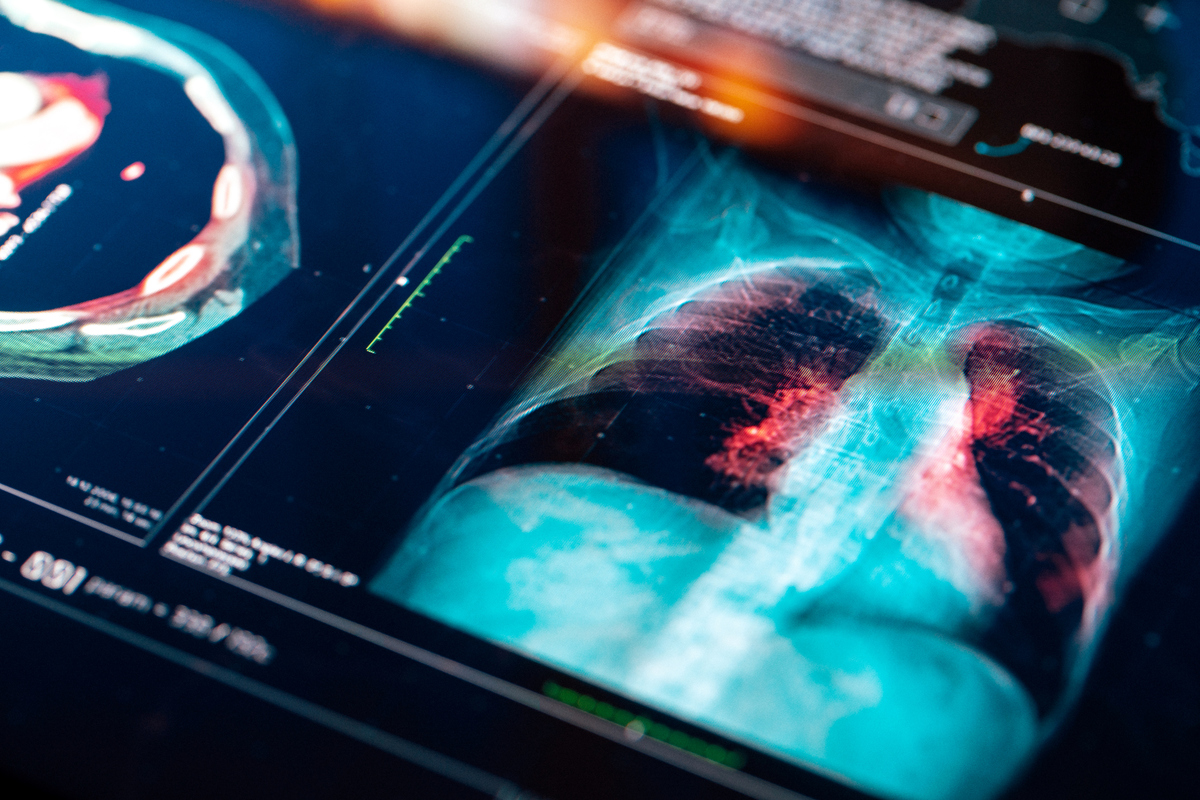

Πρόκειται για έναν τύπο καρκίνου που δεν δίνει «σήματα» από νωρίς και –δεδομένου του νυν ορίου ηλικίας για προσυμπτωματικό έλεγχο– συνηθέστερα διαγιγνώσκεται σε προχωρημένα στάδια. Τότε που οι θεραπευτικές επιλογές είναι περιορισμένες. Αν γίνει νωρίς, οι διαθέσιμες θεραπείες υπόσχονται ακόμη και ίαση.

Τα στοιχεία δείχνουν ότι πολλοί θάνατοι από καρκίνο του πνεύμονα μπορούν να αποφευχθούν, εάν τα άτομα που πληρούν τις προϋποθέσεις για προσυμπτωματικό έλεγχο υποβάλλονταν σε εξετάσεις κάθε χρόνο, ώστε να γίνεται έγκαιρα η ανίχνευση και να αυξάνονται πολύ τα ποσοστά επιβίωσης.

Διευκρινίζεται και ότι «μια αξονική τομογραφία χρησιμοποιεί ακτίνες Χ για να κάνει λεπτομερή απεικόνιση του θώρακα ενός ατόμου, συμπεριλαμβανομένων των πνευμόνων. Μπορεί να βοηθήσει στην εύρεση μη φυσιολογικών περιοχών στους πνεύμονες που μπορεί να είναι καρκίνος, προτού αρχίσουν να προκαλούν συμπτώματα».